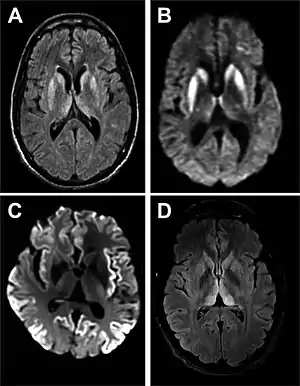

- MRI of the brain – often shows high signal intensity in the caudate nucleus and putamen bilaterally on T2-weighted images.

Imaging of the brain may be performed during medical evaluation, both to rule out other causes and to obtain supportive evidence for diagnosis. Imaging findings are variable in their appearance, and also variable in sensitivity and specificity.[41] While imaging plays a lesser role in diagnosis of CJD,[42] characteristic findings on brain MRI in some cases may precede onset of clinical manifestations.[43]

Brain MRI is the most useful imaging modality for changes related to CJD. Of the MRI sequences, diffuse-weighted imaging sequences are most sensitive. Characteristic findings are as follows:

- Focal or diffuse diffusion-restriction involving the cerebral cortex and/or basal ganglia. In about 24% of cases DWI shows only cortical hyperintensity; in 68%, cortical and subcortical abnormalities; and in 5%, only subcortical anomalies.[44] The most iconic and striking cortical abnormality has been called "cortical ribboning" or "cortical ribbon sign" due to hyperintensities resembling ribbons appearing in the cortex on MRI.[45] The involvement of the thalamus can be found in sCJD, is even stronger and constant in vCJD.[46]

- Varying degree of symmetric T2 hyperintense signal changes in the basal ganglia (i.e., caudate and putamen), and to a lesser extent globus pallidus and occipital cortex.[42]